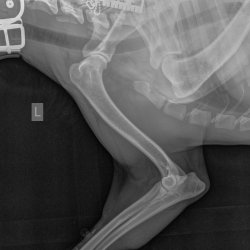

RTG snímek Rocky